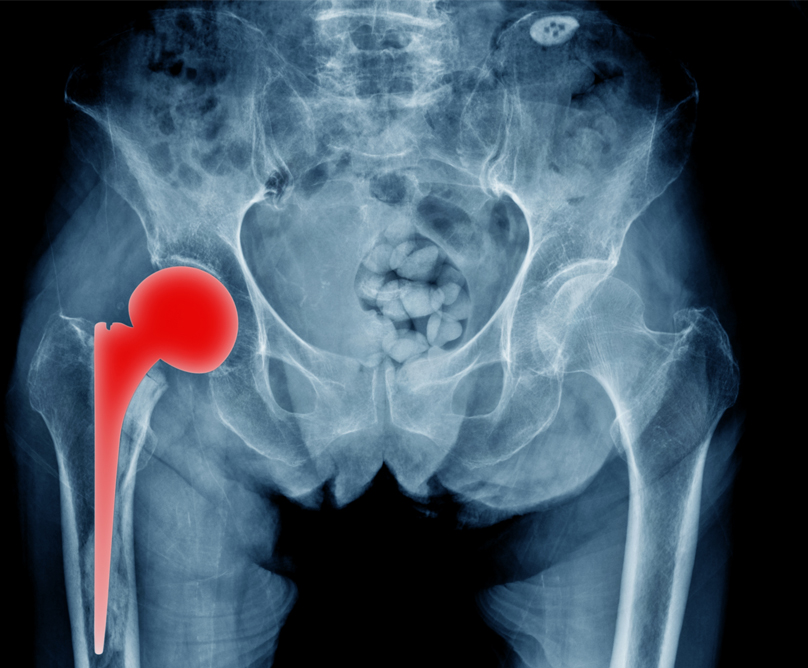

Η ολική αρθροπλαστική ισχίου είναι μια επέμβαση που κατά κύριο λόγο εφαρμόζεται ως τελική θεραπευτική λύση για την αντιμετώπιση της οστεοαρθρίτιδας του ισχίου. Η οστεοαρθρίτιδα γενικά αποτελεί μια εκφυλιστική νόσο των αρθρώσεων που επιφέρει πόνο και περιορισμό της κινητικότητάς τους. Αυτά τα συμπτώματα μπορεί να είναι τόσο έντονα που να οδηγήσουν ακόμα και σε αδυναμία εκπλήρωσης καθημερινών δραστηριοτήτων ρουτίνας.

Ολική αρθροπλαστική ισχίου

Η ολική αρθροπλαστική του ισχίου βελτίωσε και συνεχίζει να βελτιώνει την ποιότητα ζωής εκατομμυρίων ασθενών εδώ και δεκαετίες. Ωστόσο, για μεγάλο χρονικό διάστημα παρέμενε μια βαριά, συχνά αιμορραγική επέμβαση που απαιτούσε μακρά νοσηλεία και αποκατάσταση. Στην πορεία των ετών η ορθοπαιδική χειρουργική εξελίχθηκε επιστημονικά και ταυτόχρονα εξελίχθηκε και η επιστήμη των υλικών που χρησιμοποιούνται στα χειρουργεία. Αποτέλεσμα αυτών των εξελίξεων αποτελούν οι νέες χειρουργικές τεχνικές που εντάσσονται στο χειρουργικό οπλοστάσιο του ορθοπαιδικού χειρουργού για την αντιμετώπιση της οστεοαρθρίτιδας του ισχίου.